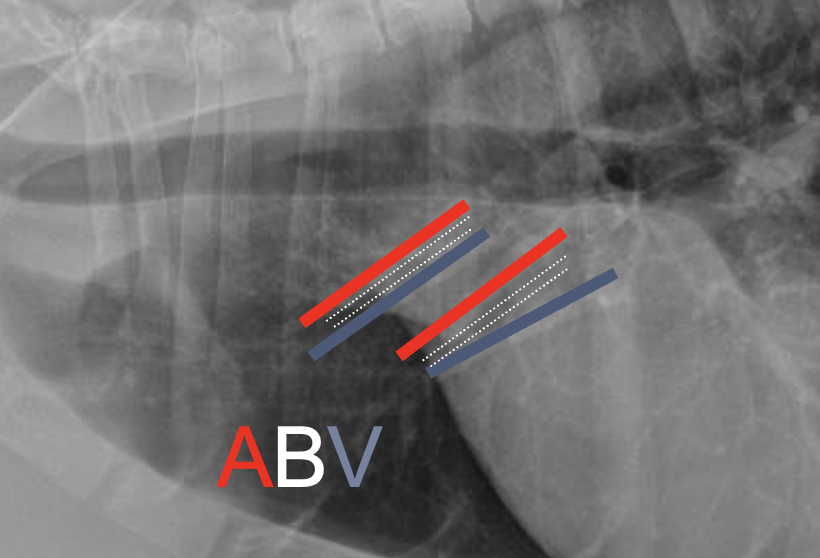

What is shown in this image?

A

arteries, bronchi, and veins in lateral view

-arteries are dorsal to bronchus

-veins are ventral to bronchus